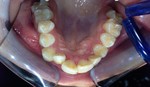

I risultati Arrivano e si vedono.

Uno dei nostri ultimi cambiamenti radicali.Il tuo sorriso può essere più vicino di quello che immagini

Total Dental MakeOver presso lo studio di implantologia sicilia del dott Gabriele Mirabella.